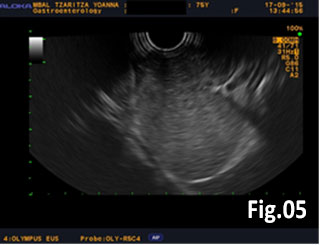

GISTs are rare mesenchymal neoplasms of the digestive tract [1,2]. They have been documented in all parts of the gastrointestinal tract, but are most common in the stomach and small intestine, followed by colo-rectum, mesentery, and esophagus [1,2]. However, the synchronous occurrence of lung cancer and GIST is extremely rare [3]. The incidence of GIST coexisting with additional malignancies is 9% to 27%, and primary lung cancer in GIST patients is 0.5%-1.2% [3]. A 75 year old woman with a smoking history for >30 years was diagnosed with advanced stage of left lung primary adenocarcinoma by chest computed tomography (CT) and bronchoscopy with sampling in February 2015 (Fig.1, Fig.2). The patient started Erlotinib 150 mg/day. In September 2015 the patient was admitted with vague abdominal pain and postprandial vomiting. Physical examination, routine blood, urine and stool investigations were unremarkable. Abdominal ultrasound detected an oval, homogenous, hypoechoic lesion 6/5/4 cm, arising from the submucosal layers of the gastric wall (Fig 3). The color Doppler demonstrated neovascularization (Fig 4). Except for 3 small simple liver cysts, no other abnormalities were present. Upper endoscopy and endoscopic ultrasound (EUS) revealed a large oval, slightly lobulated mass, hypoechoic 6x5cm between incisura angulars and greater curvature of the gastric body, originating from the 4th layer of the wall (muscularis propria). The tumor was slightly “dumbbell” shaped, protruding in and outside the stomach lumen, with several irregular hypoechoic zones and micro cysts within, looked encapsulated without infiltration of the surrounding tissues and pathologic abdominal lymph nodes (Fig. 5). A contrast-enhanced ulstrasound (CEUS) and contrast-enhanced computed tomography (CECT) of the abdomen additionally characterized the lesion and excluded liver metastases. (Fig. 6, Fig. 7) Percutaneous true-cut biopsy of the lesion was performed (18G, two separate puncture sites) (Fig 8). The immunohistochemical analysis revealed epithelioid-type GIST, diffusely positive for c-kit (CD117), with a weak focal expression of S-100 (Fig. 9). Due to life expectancy defined by the unresectable advanced lung cancer, the patient was not indicated for resection of the gastric GIST. Imatinib (Glivec) 400 mg/day was started as a “co-therapy” to Erlotinib in November 2015. After 12 months of co-treatment, a good control of both tumors was achieved. CT and abdominal ultrasound showed the gastric lesion was slightly shrunk on therapy, with large central necrosis (Fig. 10). The patient is being followed up.

Figure 5: EUS of the gastric tumor: “dumbbell” shape, irregular hypoechoic zones and microcysts, high-risk GIST suspected.